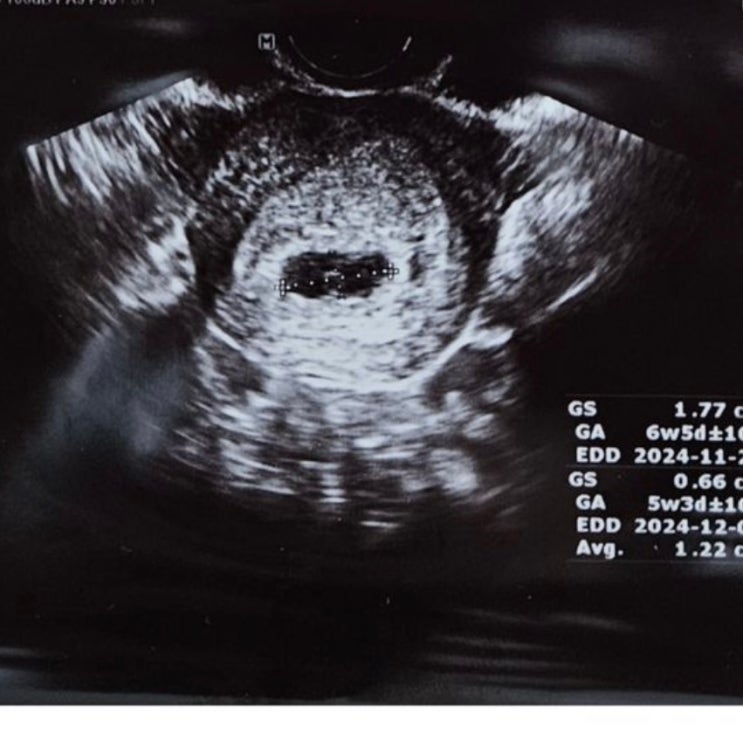

임테기 진하기 비교하기/ 아기집 보는 시기 부천서울여성병원

처음 두 줄 본 이후로는 필요 없다고 생각했던 임테기였는데 카페보다 보니 매일 또는 이틀에 한 번씩 임테...